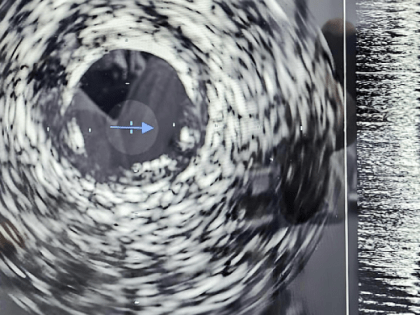

Фото правительства Кировской области О новой уникальной технологии внутрисосудистого ультразвукового исследования, которую теперь используют в Кировской областной клинической больнице сообщили в облправительстве.